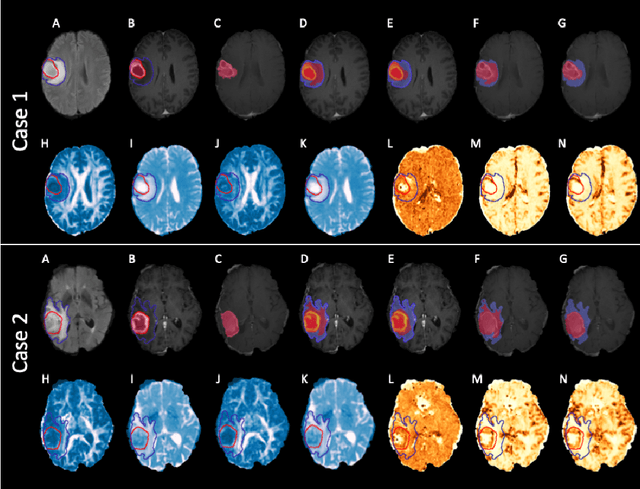

Abstract:We present an Expectation-Maximization (EM) Regularized Deep Learning (EMReDL) model for the weakly supervised tumor segmentation. The proposed framework was tailored to glioblastoma, a type of malignant tumor characterized by its diffuse infiltration into the surrounding brain tissue, which poses significant challenge to treatment target and tumor burden estimation based on conventional structural MRI. Although physiological MRI can provide more specific information regarding tumor infiltration, the relatively low resolution hinders a precise full annotation. This has motivated us to develop a weakly supervised deep learning solution that exploits the partial labelled tumor regions. EMReDL contains two components: a physiological prior prediction model and EM-regularized segmentation model. The physiological prior prediction model exploits the physiological MRI by training a classifier to generate a physiological prior map. This map was passed to the segmentation model for regularization using the EM algorithm. We evaluated the model on a glioblastoma dataset with the available pre-operative multiparametric MRI and recurrence MRI. EMReDL was shown to effectively segment the infiltrated tumor from the partially labelled region of potential infiltration. The segmented core and infiltrated tumor showed high consistency with the tumor burden labelled by experts. The performance comparison showed that EMReDL achieved higher accuracy than published state-of-the-art models. On MR spectroscopy, the segmented region showed more aggressive features than other partial labelled region. The proposed model can be generalized to other segmentation tasks with partial labels, with the CNN architecture flexible in the framework.